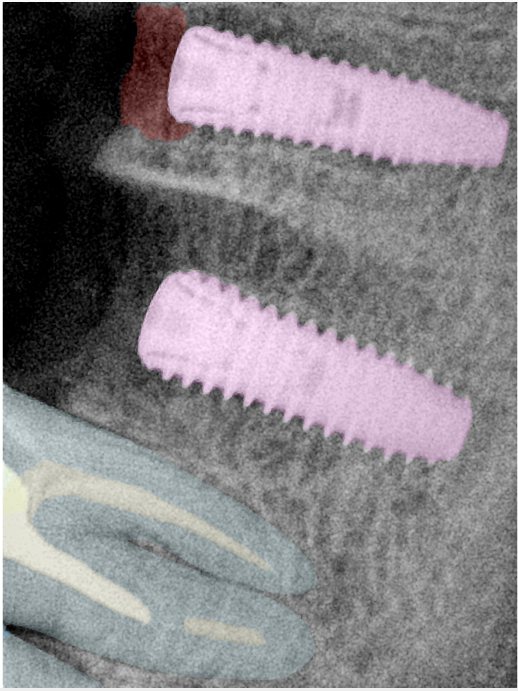

第二版算法问题测试

| 第一版 | 第二版 | 是否解决 | |

|---|---|---|---|

![]() | ![]() ![]() 边角识别有问题 龋齿识别不全 牙髓识别不全 | ![]() | 解决 |

![]() | ![]() 边角识别有问题 识别信息有误 自查(牙冠识别不全) | ![]() | 解决 |

![]() | ![]() ![]() 边角识别有误 大范围填充识别遗漏 | ![]() | 解决 |

![]() | ![]() 识别信息不全 | ![]() | 解决 |

![]() | ![]() ![]() 边角问题 牙胶识别不全 牙冠识别不全 | ![]() | 解决 |

![]() 换图片 | ![]() | ![]() 牙冠部分稍微白了一些就识别成小范围修补,部分判断异常 | 部分解决,修复类略敏感,牙冠部分稍微白了一些就识别成小范围修补,部分判断异常。 |

![]() | ![]() ![]() 牙冠识别不全 牙髓不全 根尖炎龋齿识别有误 | ![]() | 解决 |

![]() | ![]() | ![]() | 解决 |

![]() 换图片 | ![]() | ![]() | 解决 |

![]() | ![]() 牙冠识别有误 | ![]() | 解决 |

![]() 换图片 | ![]() ![]() 边角识别有误 | ![]() 修复类敏感 | 部分解决,图像过白,导致修复类判断异常。 |

![]() 换图片 | ![]() 牙冠识别不全 | ![]() 修复类敏感 | 部分解决,图像过白,导致修复类判断异常 |

结论:修复类出现了不鲁棒的情况,后续需要加入轮廓的扩充数据进行增强。